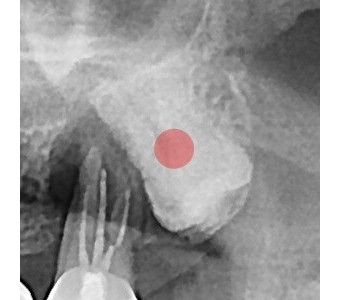

以成果证明实力。

国际摩牙齿科

真实临床案例